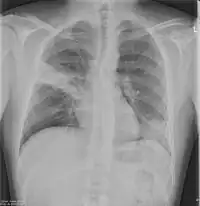

Chest X-rays and X-ray computed tomography (CT) can reveal areas of opacity (seen as white), indicating consolidation.[13] CAP does not always appear on x-rays, sometimes because the disease is in its initial stages or involves a part of the lung not clearly visible on x-ray. In some cases, chest CT can reveal pneumonia not seen on x-rays. However, congestive heart failure or other types of lung damage can mimic CAP on x-ray.[15]

When signs of pneumonia are discovered during evaluation, chest X-rays and examination of the blood and sputum for infectious microorganisms may be done to support a diagnosis of CAP. The diagnostic tools employed will depend on the severity of illness, local practices and concern about complications of the infection. All patients with CAP should have their blood oxygen monitored with pulse oximetry. In some cases, arterial blood gas analysis may be required to determine the amount of oxygen in the blood. A complete blood count (CBC) may reveal extra white blood cells, indicating infection.

Chest X-rays of a CAP patient before (left) and after treatment